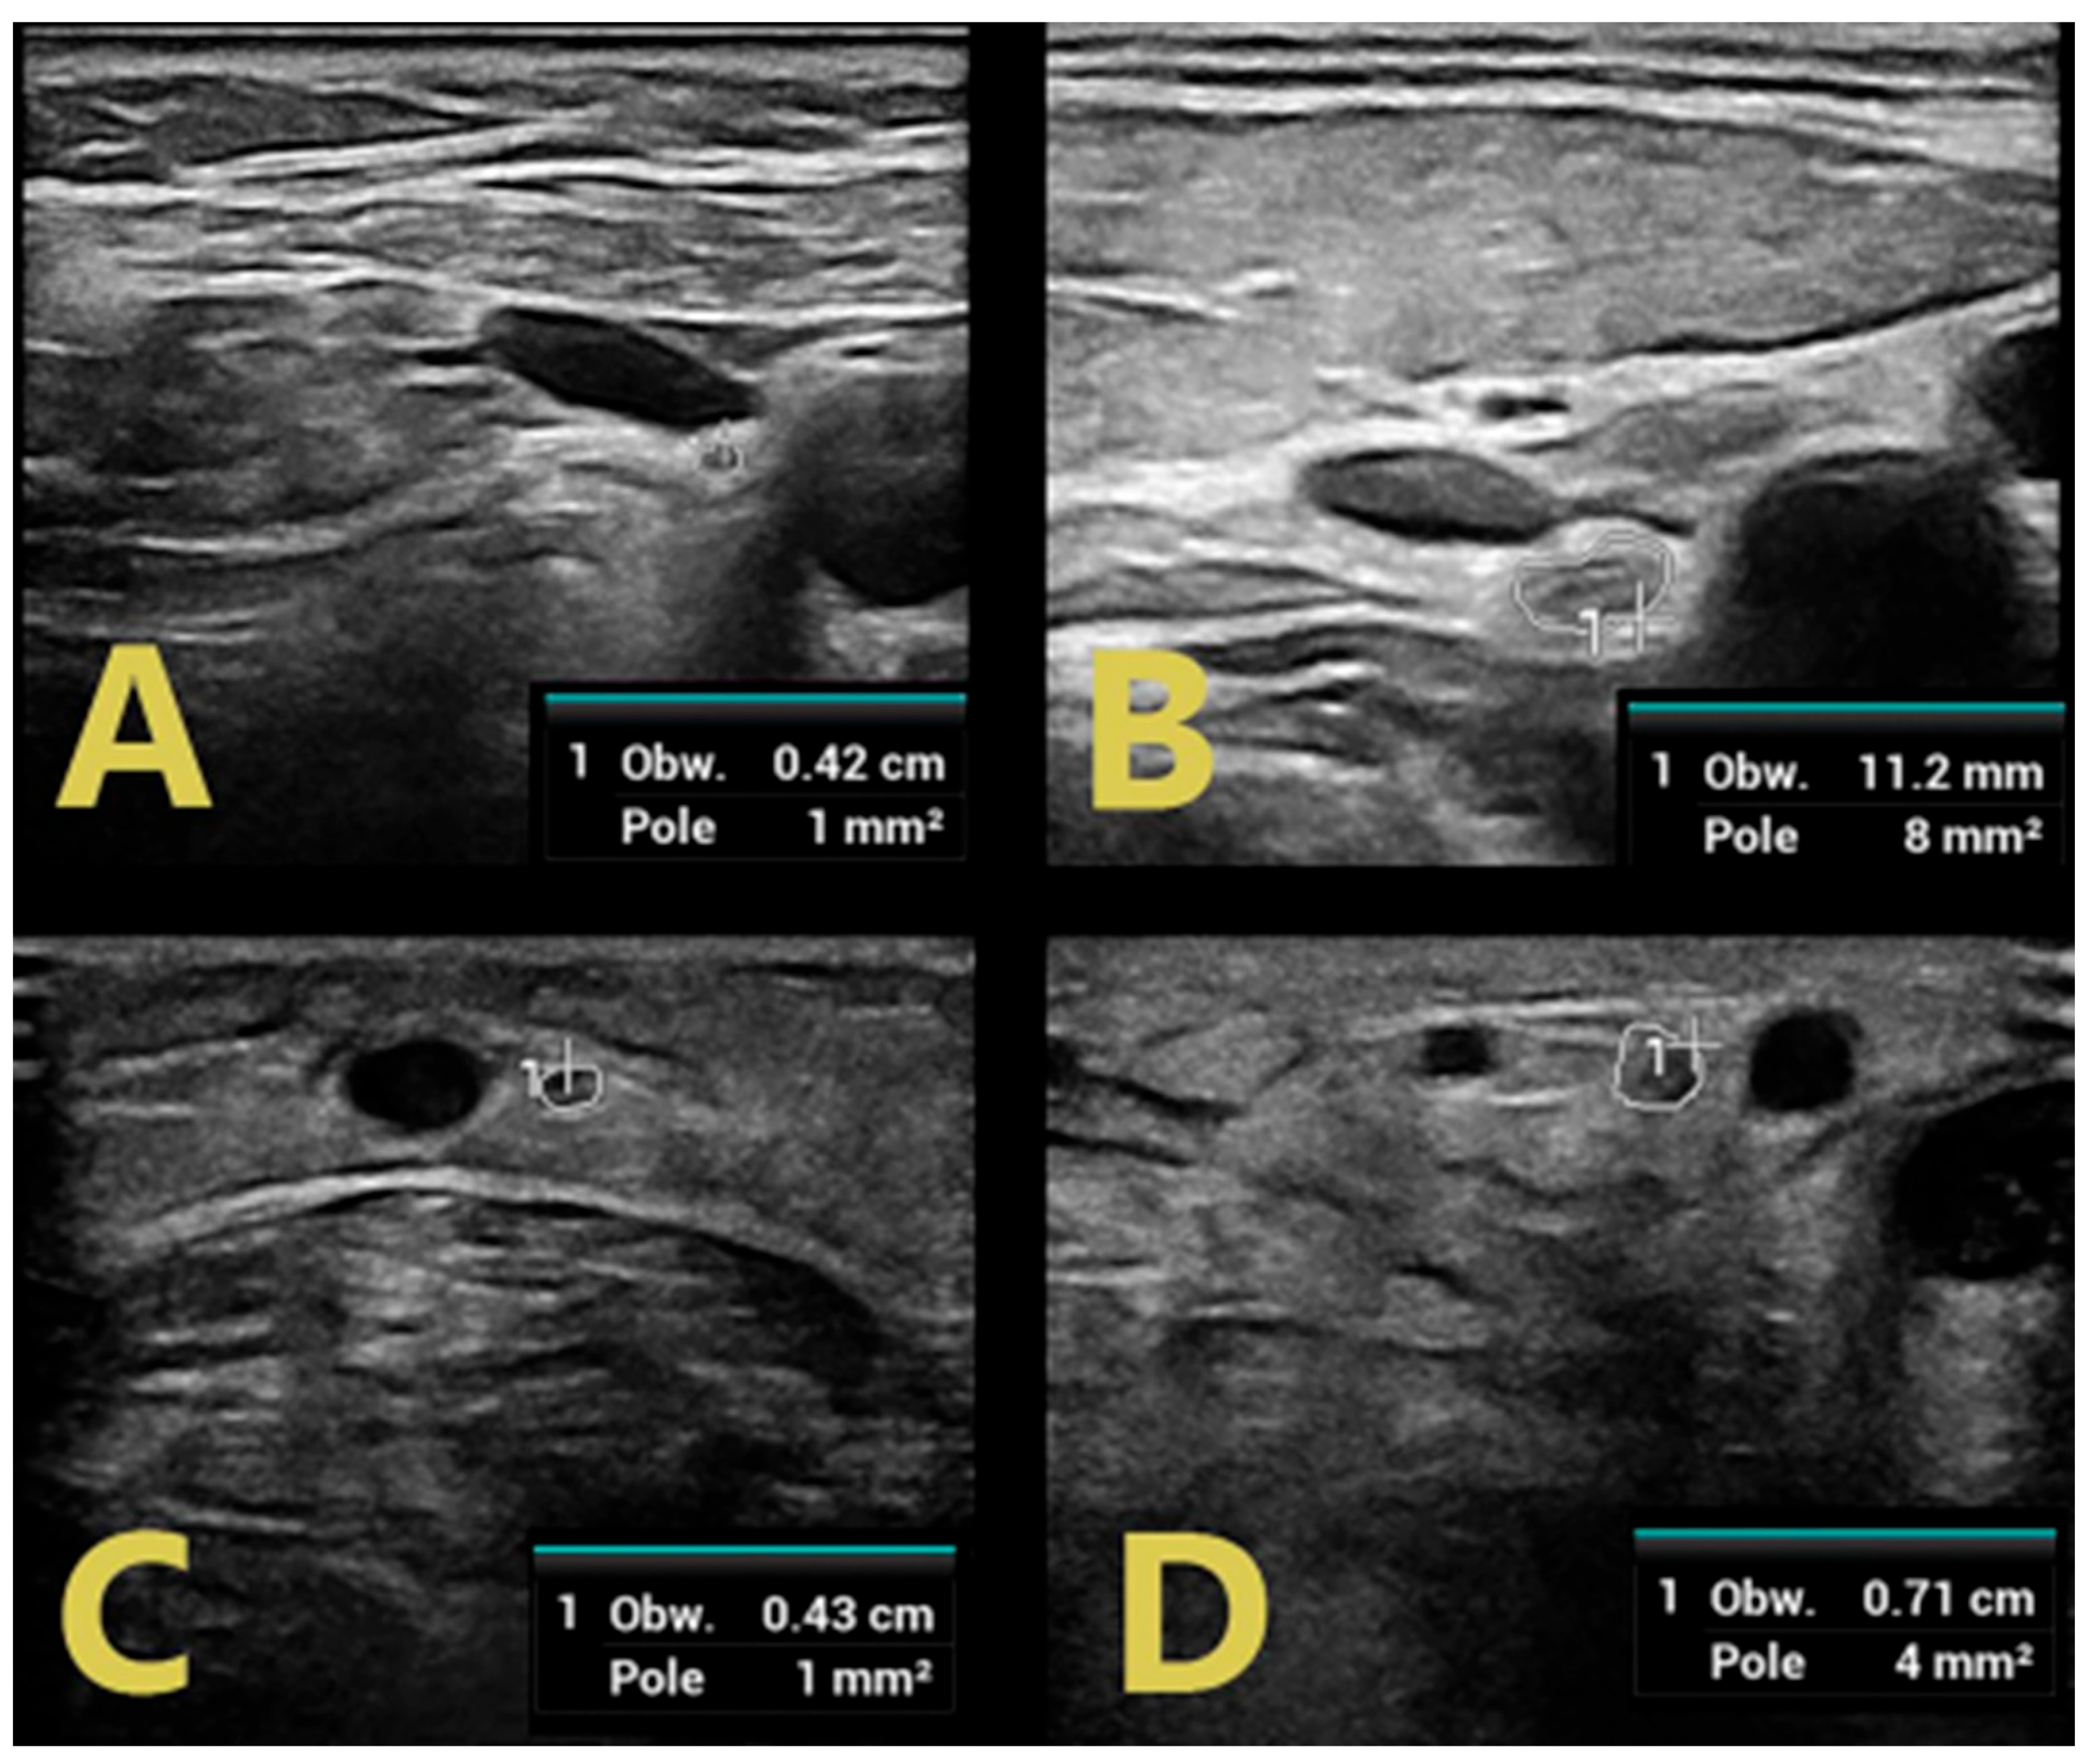

In addition, each CIDP patient showed thickening of the vagus and sural nerves; however, this was not seen in GBS patients (Figure 5). All data are presented in Table 1, Table 2 and Table 3.

Figure 5. Normal image of the vagus nerve (A) and sural nerve (C) in GBS in comparison with swelling of vagus nerve (B) and sural nerve (D) in CIDP.